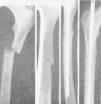

Figura 2. Fractura transversal tercio medio tibia, sin desviación, peroné íntegro, enclavijamiento cerrado; fue uno de los primeros casos tratados, y a los tres meses reanudaba el trabajo; un solo clavo mantuvo una perfecta inmovilización.

Figura 3. Fractura tercio medio tibia y peroné; enclavijamiento cerrado con un solo clavo; un tercer fragmento impide la exacta coaptación de fragmentos, obteniéndose, no obstante, una buena consolidación con predominio de callo periostal; se aprecia en la parte superior el orificio de la trepanación de entrada del clavo.